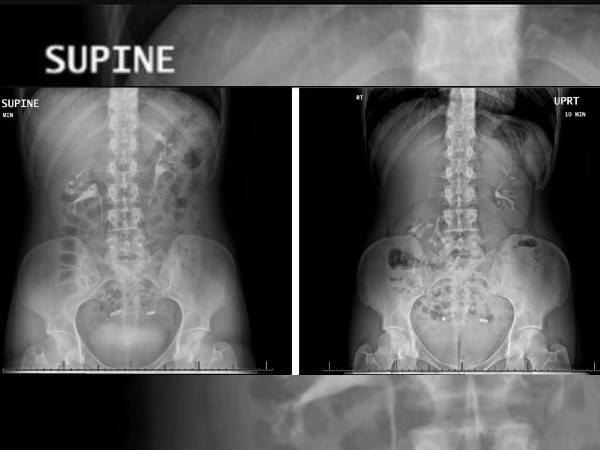

When the doctors examined her, initially they could not jump to any conclusion, as the scans revealed everything to be normal. In the scan, her kidneys appear at the same level on both sides of her spine. But the scan that was taken while she stood straight revealed the condition, as it clearly showed the woman's kidney to be floating.

The doctors revealed that her right kidney fell more than 2 inches, which is almost 6 centimetres down, or the length of two vertebrae, when she shifted positions from lying down to standing up. This was the main reason why she suffered from constant pain.